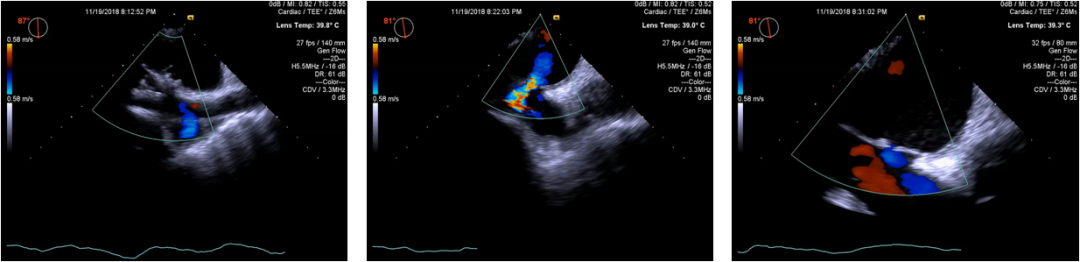

病例资料-Case 2

• Female, 52yrs

• Admissiontime: Nov.14,2018·NYHA heartfunction: III-IV

• Chiefcomplain: Exertional dyspnea for 10 year

• Pasthistory: no HTN

Echo results

病例资料-Case 3

• Female, 79yrs

• Admissiontime:Nov.12,2018

• NYHA heartfunction: III-IV

• Chiefcomplain: Exertional dyspnea for 1 year

• BP:126/64mmHg,heartrate:56bpm

• Bloodtest: normal

• ECG: Sinusrhythm

• TEEexcludes left atrial thrombosis

• Coronaryartery CTA: normal